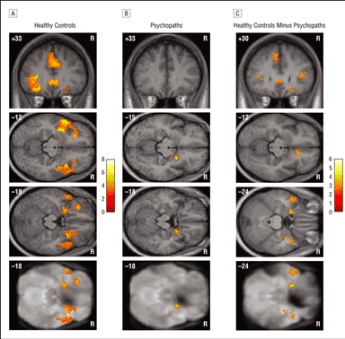

In addition to difficulty in recognizing fear, those with psychopathic traits report less subjective fear in threatening scenarios [2]. This finding extends to both the brain as well as the body’s physiological response. In one particular MRI study, researchers compared a group of healthy control subjects to a group of criminal offenders who scored highly on the PCL-R, an exam widely used to assess psychopathic traits. Both groups underwent “fear conditioning” in which they were trained to associate an aversive stimulus (painful pressure) with pictures of neutral faces.

A figure adapted from [3] showing the differences in brain activity between healthy controls and psychopathic individuals during fear conditioning